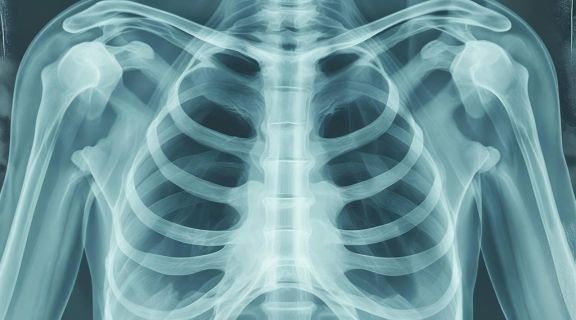

Os métodos de diagnóstico incluem exame físico, exames de imagem (como radiografias de tórax, tomografias computadorizadas e ressonância magnética), exame do interior do pulmão por meio de broncoscopia, coleta de amostra de tecido (biópsia) para exame histopatológico e definição do subtipo específico (CPNPC versus CPCP) e testes moleculares para identificar mutações genéticas específicas ou biomarcadores que orientem a melhor opção de tratamento.